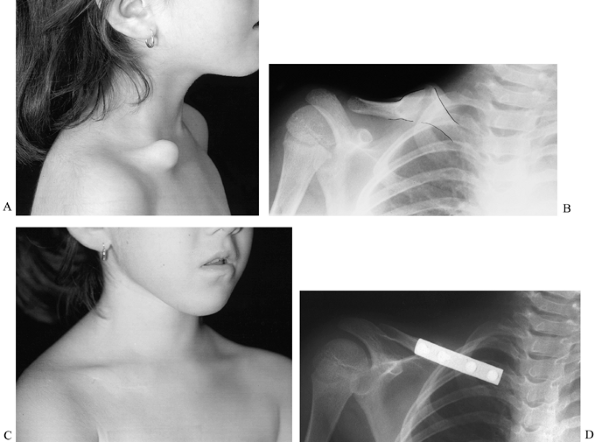

have a prominent middle third of the right clavicle at birth or soon

thereafter; the prominence may increase with age (146).

The pseudarthrosis is usually not painful, and shoulder range of motion

is normal. Radiographs of the pseudarthrosis reveal an osseous

separation with enlarged, rounded bone ends, and a distinctive absence

of fracture callus (Fig. 165.32). Although case reports indicate that the natural history of pseudarthrosis of the clavicle is benign (151), no large series of cases has been reported.

![]() |

Figure 165.32. Congenital pseudarthrosis of the clavicle. A: Preoperative photo. B: Preoperative radiograph (pseudarthrosis outlined). C: Postoperative photo. D: Postoperative radiograph.